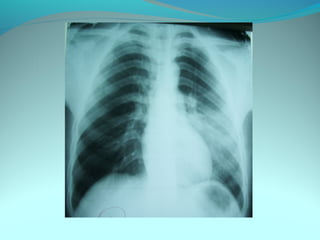

Image radiologique bilaterale

A droite : clarté sous claviculaire et axilaire droite arrondie de 3 cm de

diam entourée d une paroi de 4mm d’épaisseur

Le 1/3 sup du poumon droit est le siege d’opacité nodulaire avec

quelque clarté

A gauche: le 1/3 moyen est le siege d’opacité nodulaire et de clarté de

taille variable

DIAGNOSTIC:

Tuberculose pulmonaire bilaterale cavitaire